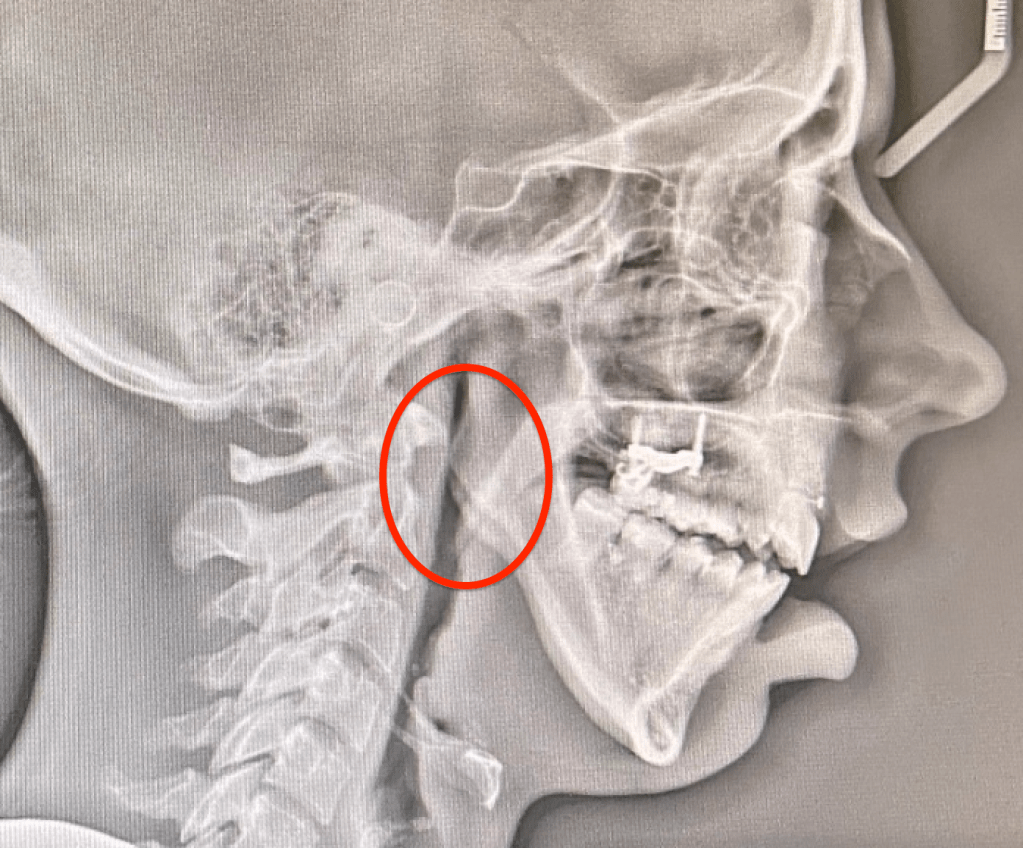

- Past pain patterns: My old pain patterns are STILL not presenting themselves!! I am so happy about this!!!!!! I figured out now that I am on the other side of this, that my MANDIBLE was pressing hard on all my neck muscles, it was so far back on my neck from losing the 75% of my condyles on both side over the last 20 years. It was probably causing most of my radiating pain in the final years. Joint pain was starting to get worse as well, but it wasn’t as “searing” as it was in 2016 before my fat graft diskectomies.